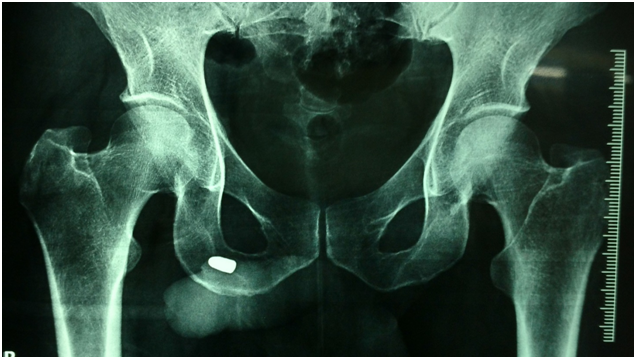

45 years male with a history of a gunshot fired from the left side of the hip with a retained bullet in the penis. On evaluation no history of hematuria, no difficulty in walking. On examination, entry wound was found on the left side of buttock with no other injury mark except bruise at the base of the penis. The bullet was seen in the distal part of the penis on X-ray pelvis (Figure 1). No hematuria was seen. Retrograde urethrogram was normal. Pelvic X-ray was normal except the retained bullet was seen in the distal part of the penis (Figure 2). The bullet was removed from the penis under local anesthesia. Postoperative period was uneventful (Figure 3).

Figure 1 X-ray AP view showing bullet in penis.